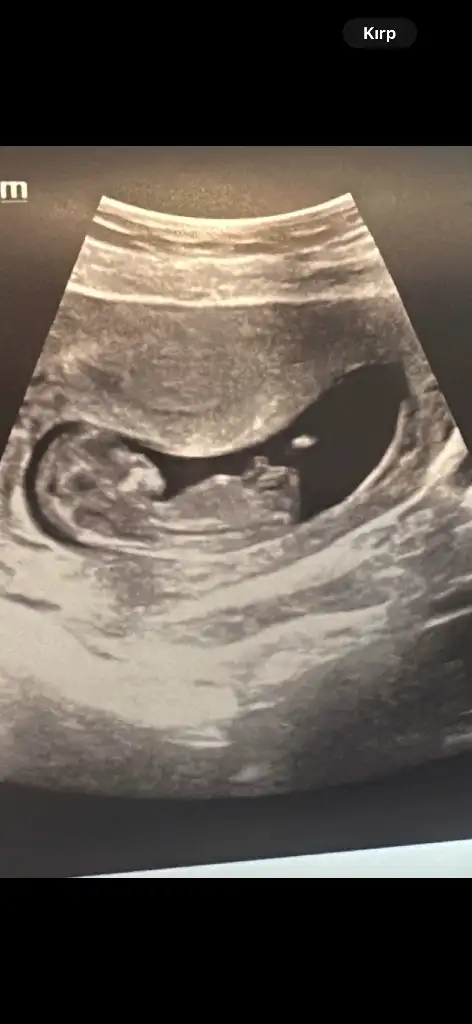

Lütfen bana da bir yorum yapar mısınız. Karından. 13+4 haftalık. İki kızım var erkek olsun istiyorum 🙈

Eklentiler

• IMG_20250307_073925.webp

IMG_20250307_073925.webp

22,9 KB · Görüntüleme: 150